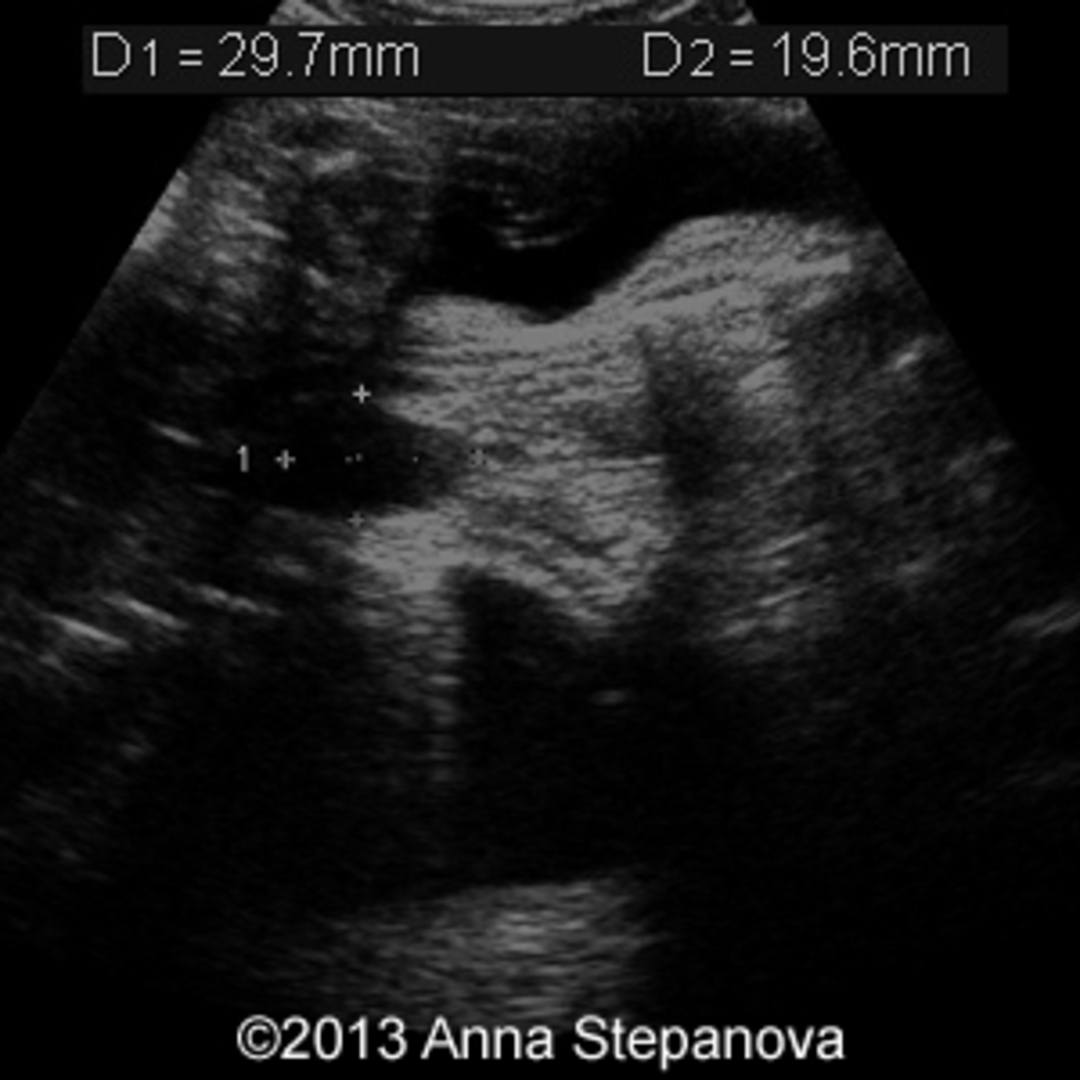

From www.researchgate.net

Ultrasound image of the horseshoe kidney Download Scientific Diagram Horseshoe Kidney In Fetus horseshoe kidney is when the 2 kidneys join (fuse) together at the bottom. horseshoe kidney, also called renal fusion, is a condition that starts before a child is born. horseshoe kidney is a condition that develops when a fetus is still growing inside the uterus. As a baby develops in the. horseshoe kidney occurs during fetal. Horseshoe Kidney In Fetus.